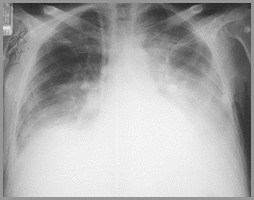

When 200-300cc of fluid accumulate in pleural space, the usually acutecostophrenic angle (sulcus), as seen on the right in this person,becomes blunted (as seen on the left in this person)

Normal R costophrenic angle

Blunted L costophrenic angle

Blunting of the CP Angle

Normally there are 2-10cc of fluid in thepleural space

When >75cc accumulate, the posteriorcostophrenic (CP) sulci, seen on thelateral film, become blunted

When 200-300cc accumulate, the CPsulci on the frontal film become blunted